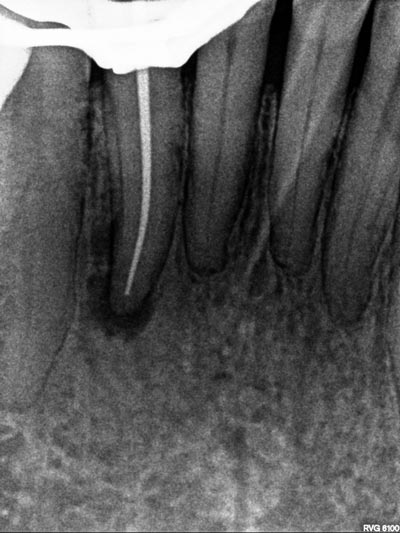

Imágenes: Endodoncia en un incisivo inferior calcificado y necrótico.